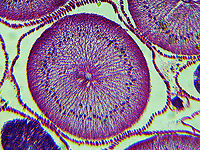

Roundworm (Female) with Labels - Ascaris lumbricoides

*Microscope slide; cross-section

''Ascaris lumbricoides'' is the "large roundworm" of humans, growing to a length of up to 35 cm. It is one of several species of ''Ascaris''. An ascarid nematode of the phylum Nematoda, it is the most common parasitic worm in humans. This organism is responsible for the disease ascariasis, a type of helminthiasis and one of the group of neglected tropical diseases. An estimated one-sixth of the human population is infected by ''A. lumbricoides'' or another roundworm. Ascariasis is prevalent worldwide,.. more